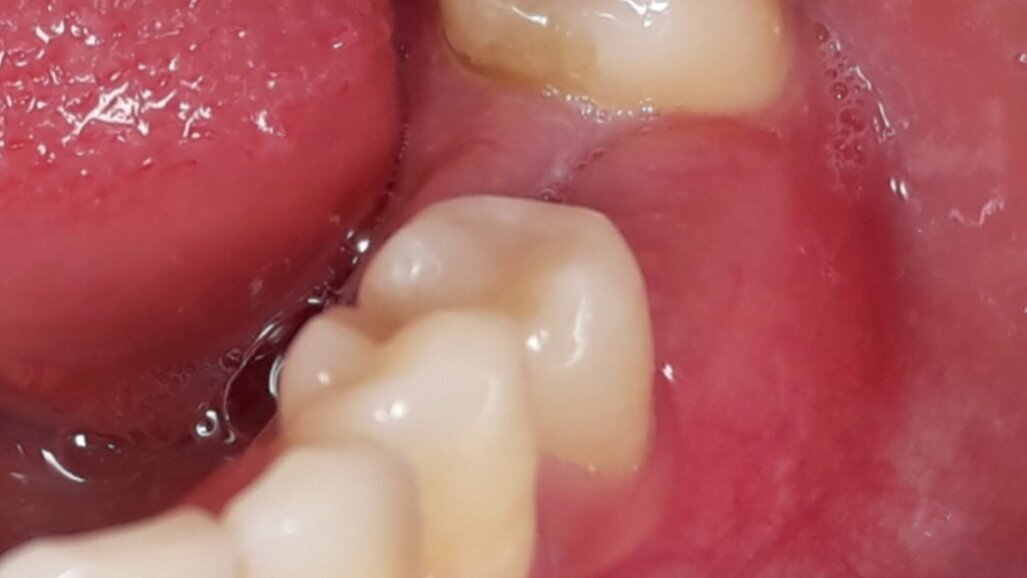

Nello studio sono stati inclusi 20 pazienti (12 donne e 8 uomini) di età compresa tra i 28 e i 65 anni, con edentulia singola e conseguente deficit vestibolare dei tessuti molli. La matrice dermica a elevata consistenza è stata opportunamente ritagliata mediante forbici e lama ed è stata posizionata al di sotto del lembo muco periostale allestito con approccio a spessore totale, vestibolarmente alla cresta ossea in cui è stato posizionato contestualmente un impianto endosseo osteointegrabile. Non si è utilizzato alcun ausilio di fissazione per la matrice dermica che è stata stabilizzata dal solo lembo di accesso ribaltato su di essa e suturato, mediante punti staccati semplici, al lembo linguale.

Le rilevazioni eseguite a distanza di 18 mesi di tempo medio, hanno mostrato un netto miglioramento del PES (Pink Esthetic Score) con un punteggio medio superiore a 9 (eccellente) e in due casi un punteggio tra 6 e 8 (buono). La sovrapposizione dei file .stl provenienti dalla scansione della arcata dentaria interessata prima dell’intervento e a distanza di 18 mesi ha permesso di rilevare un incremento medio in senso orizzontale di 2 mm in media.